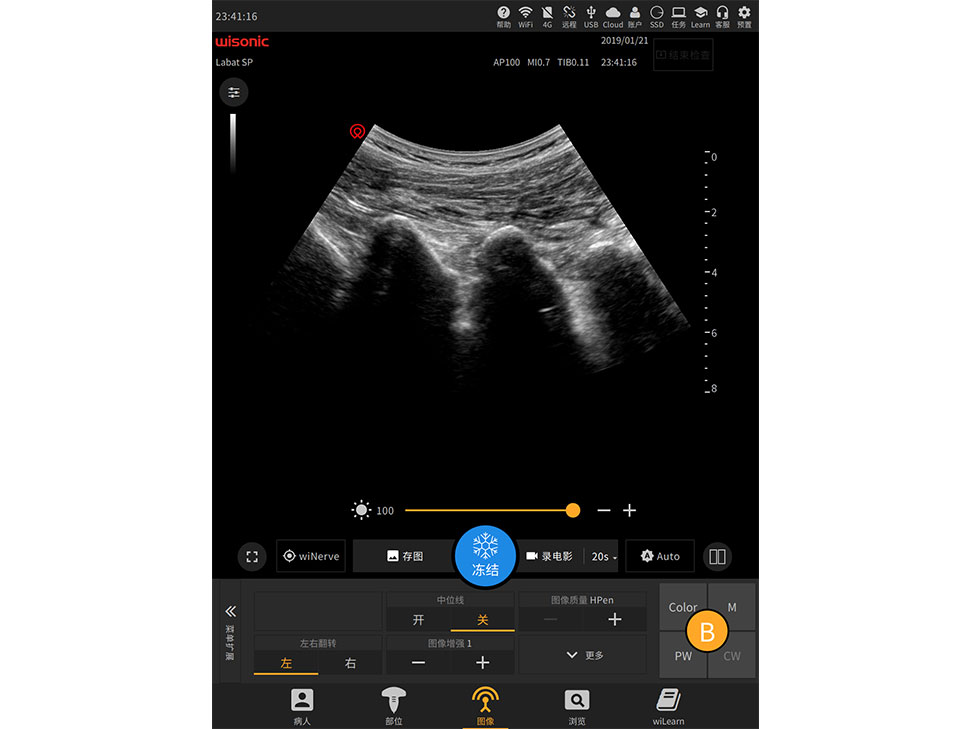

übersicht

Excellent Clinical Images

Anwendungsbilder